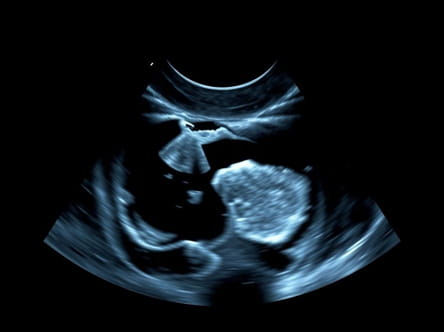

Role of Ultrasound in Diagnosing Capsular Contracture

Ultrasound imaging is a non-invasive diagnostic tool that uses high-frequency sound waves to create detailed images of the breast tissue and implant. It is particularly valuable for evaluating capsular contracture because it allows clinicians to visualize the thickness of the capsule, detect fluid accumulation, and assess implant integrity without exposure to radiation. Some key advantages of ultrasound for capsular contracture include